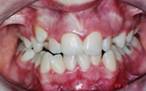

Antes

DepoisCorreção feita bem cedo, com o uso de aparelho ortopédico funcional.